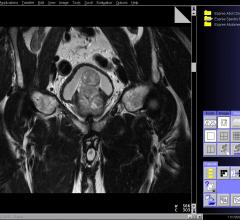

News and new technology innovations concerning how imaging technology can help diagnose and treat prostate cancer can be found on this channel.